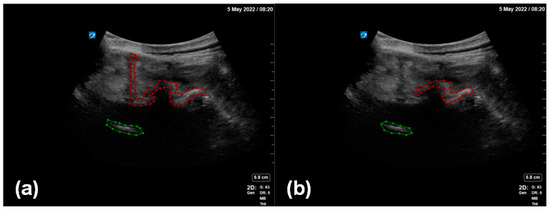

Two professional anesthesiologists confirmed the inclusion of a facet joint and ventral complex in all the image data and processed the ultrasound image data to remove the patient’s name, physician’s unit, and physician’s name. Under the review and proofreading of the senior anesthesiologist, the annotator marked the outline of the facet joint and the ventral complex in each image. The marking software used in this study was LabelMe (version 4.5.13), an open annotation tool. In this study, we proposed an enhanced data annotation method for the facet joint using the facet joint as the first target and the ventral complex as the second target (Figure 3). In order to evaluate the influence of data annotation on deep learning, we considered two labeling manners: (i) a local labeling method (Figure 3b), which only involved facet joints and ventral association; (ii) a full labeling method (Figure 3a), which involved transverse processes, facet joints and even bone structures in the median line and ventral association.

Figure 3. Two methods of enhanced data annotation: (a) full labeling method; (b) local labeling method. The red annotation indicates the facet joint, and the green annotation indicates the ventral complex.